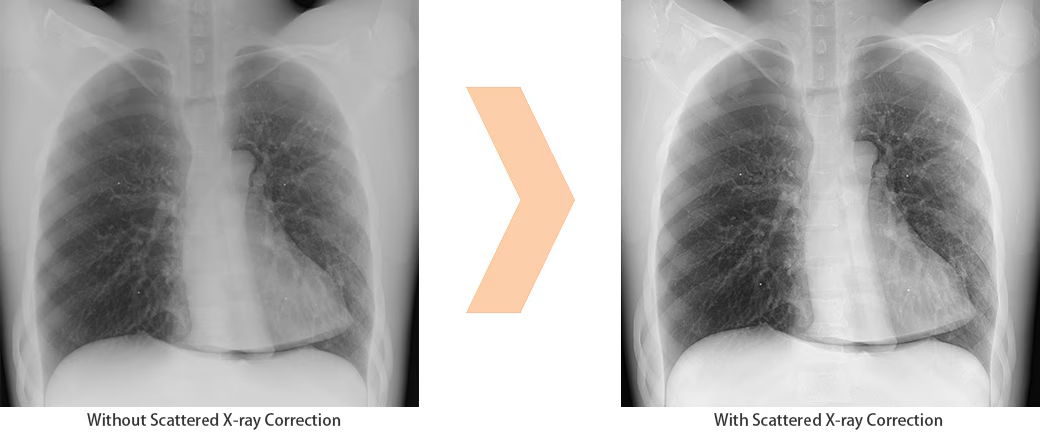

Scatter Correction enables grid-less radiography OPTION

The system can be equipped with a function to remove scatter noise and improve image contrast, making it possible to perform exposures without the use of a grid therefore making it easier to handle FPDs.